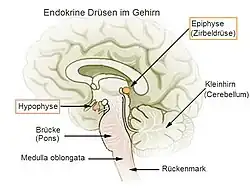

Die Zirbeldrüse oder lateinisch Glandula pinealis, kurz Pinealis oder Pinea – nach der Form der Zapfen der Zirbelkiefer (Pinus cembra) bezeichnet[1] –, anatomisch auch Epiphysis cerebri oder kurz Epiphyse genannt (weitere synonyme Fachausdrücke siehe unten), ist eine kleine, häufig kegelförmige endokrine Drüse auf der Rückseite des Mittelhirns im Epithalamus (einem Teil des Zwischenhirns).

Anatomie

Die Zirbeldrüse liegt als unpaares Gebilde mitten (median) im Gehirn an der Hinterwand des III. Ventrikels über der Vierhügelplatte. Sie gehört zu den zirkumventrikulären Organen und wird anatomisch als Glandula pinealis sowohl zu den endokrinen Drüsen[2] gezählt, wie auch dem Epithalamus[3] zugeordnet.